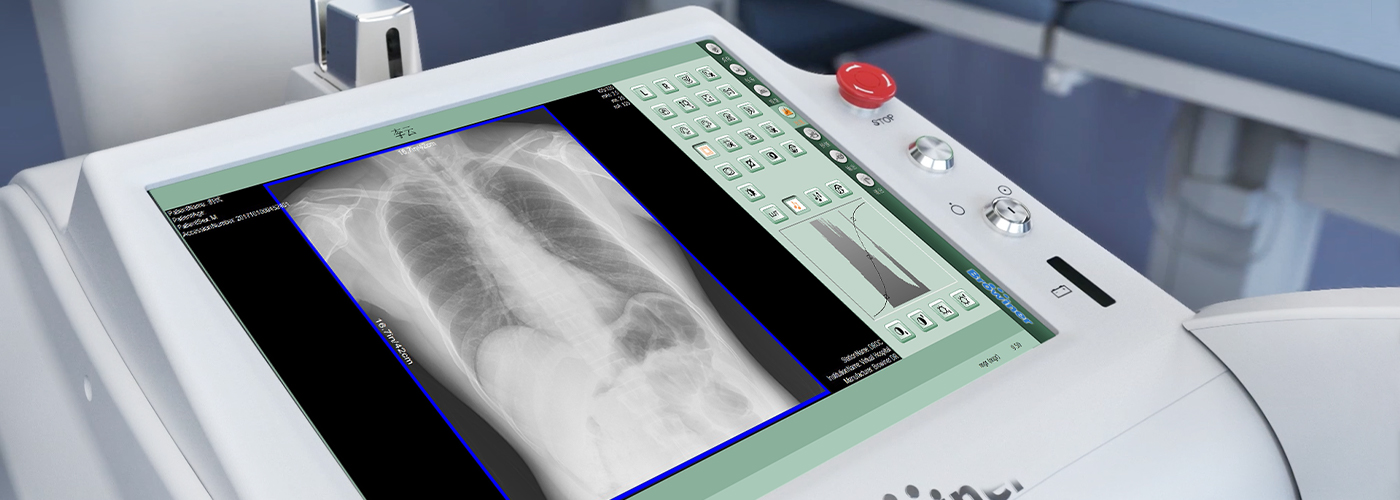

操作流畅 清晰呈现

搭载大尺寸触摸屏,大视野,操作更加流畅便捷,清晰呈现更多细节。